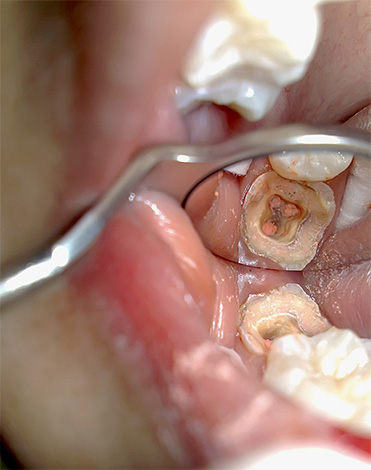

durante carie iniziale il nervo non è ancora interessato, ma con approfondire il processo cariato i batteri alla fine entrano nella camera della polpa, causando qui un'infiammazione: la pulpite. Allo stesso tempo, una persona può provare forte dolore, spesso peggio di notte.

pulpite (infiammazione del "nervo" del dente) è una malattia che richiede quasi sempre la rimozione parziale o completa della polpa interessata dal dente al fine di evitare un'ulteriore diffusione dell'infezione oltre la radice, che potrebbe portare allo sviluppo di gravi complicanze.